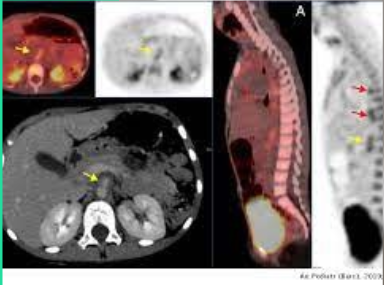

• Combinación de PET con TAC

Combinación de PET con TAC

Surge la combinación de PET con TAC data cuando asociado al equipo se corregían con mayor se comprobó que utilizando la imagen de un TAC de muy baja dosis precisión los problemas de atenuación intrínsecos a la imagen PET